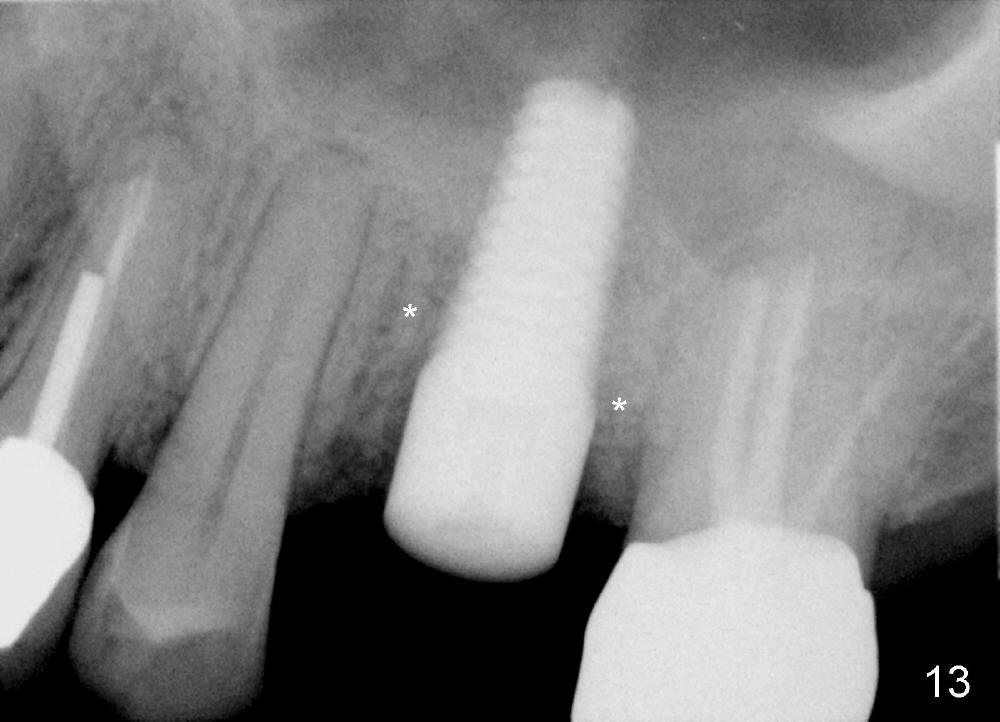

Four months postop, bone around the implant looks consolidated (Fig.13 *, compare to Fig.2,5).